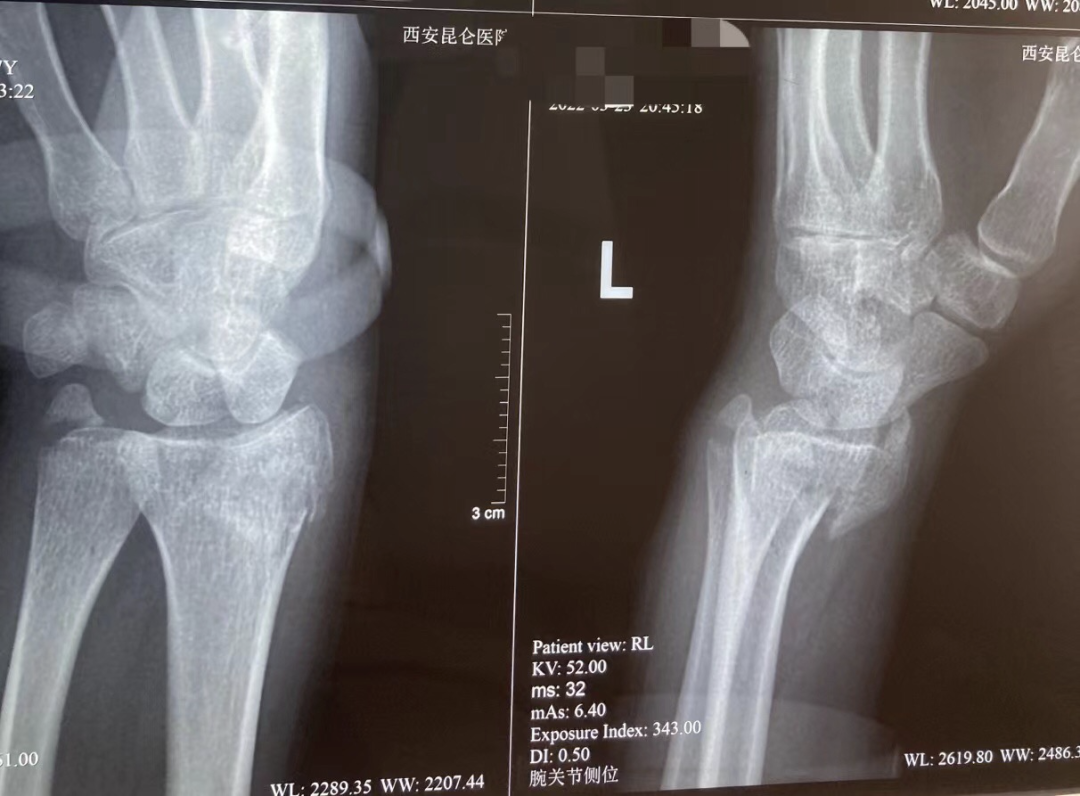

被撞倒的后座女乘客,经拍片后确认为左手骨折。